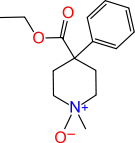

4-Phenylpiperidines

Pethidines (meperidines)

- Meperidine-N-oxide

Structures